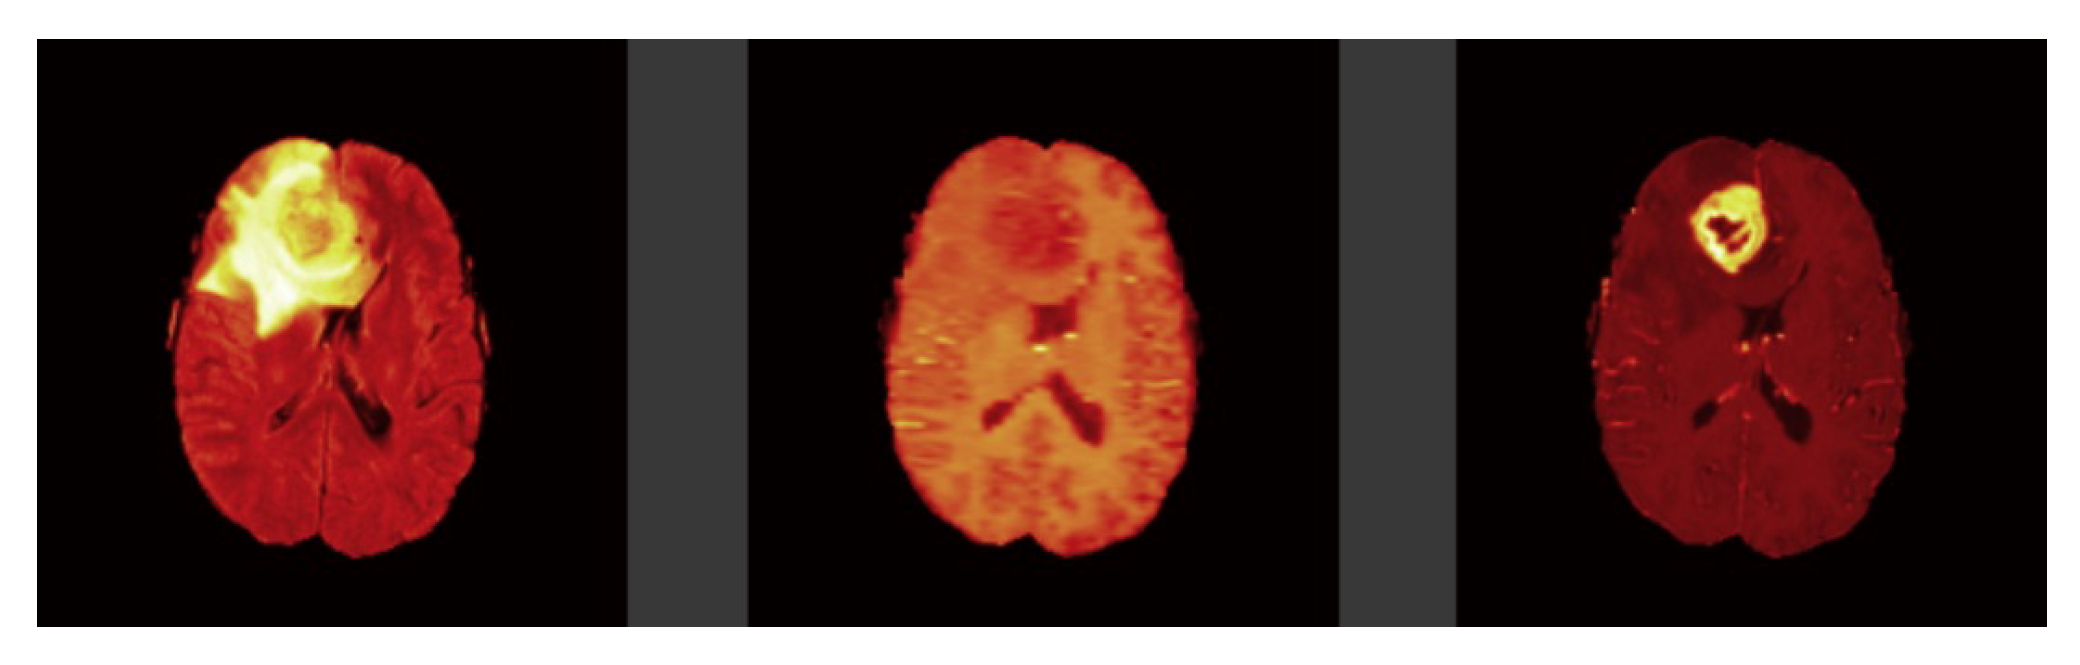

Figure 1.

Brain tumor modalities. (Left image: FLAIR, Middle image: T1-weighted, and Right image: T1ce respectively).

Tl-weighted is basically used to distinguish between healthy and diseased tissues, and these scans offer a distinction between gray and white matter Figure 1. T2-weighted are well matched to brain disorders in which water accumulates within brain tissues due to the vulnerability of this modality to water content Figure 2. This modality determines the area of the edema, resulting in the generation of a bright signal on the image. Colorless fluid found in the spinal cord and brain known as cerebrospinal fluid (CSF) can be separated effectively using T1 and T2-weighted images. In T2-weighted images this CSF looks bright, and in T1-weighted images look dark. T1-weighted MRI with gadolinium contrast enhancement (T1-Gd) is the fourth type of MRI sequence. In this modality, an accumulated contrast agent, such as gadolinium ions, is used in the active cell area of the tumor tissues to produce a bright signal that facilitates the demarcation of the tumor boundaries. Since necrotic cells do not associate with contrast agents, they are segregated as a hypo-intense part of the center of the tumor, and this promotes the segmentation of the hypo-intense part of the active cell zone. FLAIR, with the exception of its acquisition protocol, is identical to T2-weighted images. Here the suppression of the water molecule is achieved, which in turn helps to discriminate between the edema and the CSF. FLAIR has the capacity to block water signals, and the hypertensive periventricular lesion is easily visible.